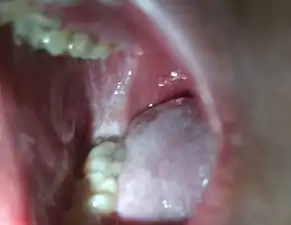

Koplik's spots seen inside the mouth are diagnostic for measles, but are temporary and therefore rarely seen.[28] Koplik spots are small white spots that are commonly seen on the inside of the cheeks opposite the molars.[27] They appear as "grains of salt on a reddish background."[30] Recognizing these spots before a person reaches their maximum infectiousness can help reduce the spread of the disease.[31]